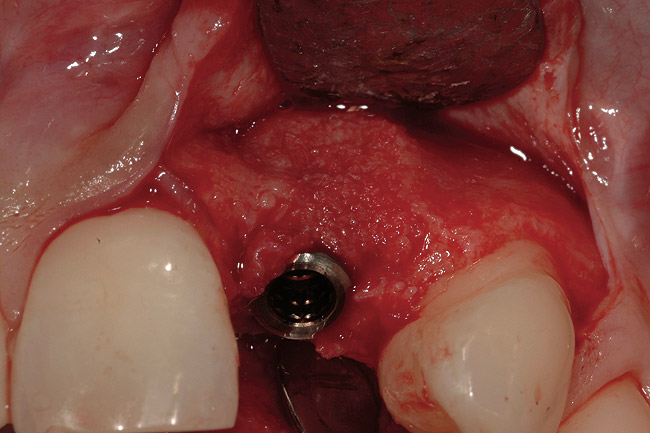

Figure 6  Alveolar ridge form permitted optimal implant placement (5 months posttreatment).

Figure 6

From a clinical perspective, the primary challenge was the development of an esthetic emergence of the dental implant-supported crown restoration. Maintenance of the soft-tissue dimensions, therefore, was critical to the treatment success. In an effort to optimally maintain the ridge form, a connective tissue graft harvested from the palate39,40 was placed over the collagen membrane to augment the soft tissues. Then, the buccal flap was advanced to achieve primary closure. Postoperative healing proceeded uneventfully. The overlying soft tissue exhibited rapid clinical closure and healed with minimal evidence of the surgical procedure. The clinical outcome was also consistent with development of the desired ridge form. Cone-beam computed tomography imaging revealed an alveolar ridge form that was optimal for implant placement at 5 months post-treatment. The radiographic density of the augmented region was similar to the adjacent native bone, with no discernable interface between native and apparent new bone, consistent with integration and remodeling. Surgical re-entry for implant placement revealed the optimal ridge form (Figure 6 ). The implant was allowed to integrate for 5 months prior to the healing abutment placement and interim restoration. The overcontoured soft tissues enabled surgical sculpting to achieve the desired contour for the restorative emergence. A highly acceptable esthetic result was achieved. With preservation of the marginal and papillary gingival contours (Figure 7 and Figure 8 ); the radiographic presentation was consistent with normal bone remodeling and implant integration.